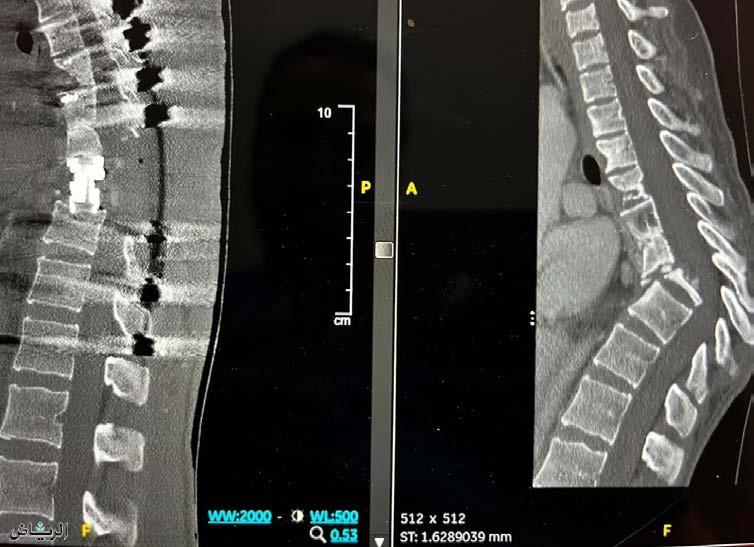

2023 )وينوي( ناريزح l 30 دوعس كللما ةعماجب ةيبطلا ةنيدلما ةيلفسلا فارطلأا في لماكلا للشلا نم باش ذاقنإ ءاضعلأا ةعارزل يدوعسلا زكرلما يوضعلا روصقلا ضىرم نم ةنطاومو انطاوم11 ةايح ذقنت ةعارز ةيلمع 12 ةيبطلا ةنيدلما في يبط قيرف حجن ةيحارج ةيلمع ءارجإ في دوعس كللما ةعماجب فارطلأا في ئجافلما للّشلا نم نياعي باشل .ةيلفسلا فنجلاو يرقفلا دومعلا ةحارج يراشتسإ حضوأ ئراوط ىلإ لصو باشلا نأ ينرقلا رازن روتكدلا في ءاضعلأا ةعارزل يدوعسلا زكرلما قيرف حجن ءاضعلأاب عبرتلا لىع ةقفاولما لىع لوصحلا ىفشتسم نم لك في ايغامد ينفوتم ةثلاث نم ىفشتسمو ،يديوسلاب بيبحلا نمايلس روتكدلا يرملأا ىفشتسم لىإ ةفاضلإاب ضايرلاب ةلد .فوجلاب زيزعلادبع نب بعتم 50و 49 رمعلا نم ناغلبي نينطاوم ةايح ذاقنإ ىرجو يتيلمع ءارجإب كلذو يبلقلا لشفلا ضرم عم اماع نيرخآ نينطاوم ةايح ذاقنإ مت امك ،امهل بلق ةعارز يدبكلا روصقلا عم 64و 49 رمعلا نم ناغلبي نيتئر ةعارز ةيلمع ءارجإ ىلإ ةفاضلإاب يئاهنلا نم يناعي وهو يعماجلا دلاخ كلملا ىفشتسم يف فعضو ليمنت عم رهظلا فصتنم يف ملاآ ةيلولأا تاصوحفلا ءارجإ دعبو .ةيلفسلا فارطلأا ةسداسلا ةيردصلا ةرقفلا يف امرو هيدل نأ نيبت باشلا رمعل ةبسنلاب ةردانلا مارولأا نم عون وهو لبحلاب مرولا طيحي ثيح ،اماع 17 غلبي يذلا ديدش طغضب ببست ام ،لماك لكشب يكوشلا نم هتايح ذاقنلإ اماع 56 رمعلا نم غلبي نطاومل .يئاهنلا يوئرلا روصقلا ضرم ةاناعم تهنأ ىلك ةعارز تايلمع 6 كلذك تيرجأ ضرمب هتباصإ ءارج ماوعأ ةتس رمعلا نم غلبي لفط ،هل ىلك ةعارز ةيلمع ءارجإب كلذو يولكلا روصقلا اماع 64 رمعلا نم غلبت ةنطاوم ةاناعم ءاهنإ متو يومدلا ليسغلا تاسلجو داحلا يولكلا روصقلا عم تايلمع ثلاث ءارجإ متو ،اهل ةيلك ةعارز ةيلمع ءارجإب عم تاونسل اوناع نيرخآ نينطاوم ةثلاثل ىلك ةعارز يتيلمع ءارجإ ىلإ ةفاضلإاب يولكلا لشفلا ضرم نم غلبي رخآ نطاومل سايركنب ةعارزو ىلك ةعارز افيضم ،ةرقفلا يف رسكب تببست تافعاضم عم باشلا ةلاح تمقافت صيخشتلا تاءارجإ للاخ هنأ فارطلأل لماكلا للشلا ىلإ ىدأو عيرس لكشب ةقطنم نم لماكلاب ساسحلإا دقفو ةيلفسلا .نود امو ردصلا مرولا ةلازإ اهللاخ ىرج ةلجاعو ةقيقد ةيلمع ءارجإ مت ريرحتو ،لماك لكشب يكوشلا لبحلا ىلع طغاضلا تيبثت عم ةطيحم تاطوغض يأ نم يكوشلا لبحلا دق ةكرح يأ عنمل ةصاخ ريماسمب ةيردصلا تارقفلا حاجنلاب تللكت ةيلمعلا ؛يكوشلا لبحلا يفاعت قيعت مسج نم يلفسلا ءزجلل ساسحلإاو ةكرحلا تداعو تاسلج دعب لماك لكشب ىفاعت دقو ،باشلا جلاعلا ىقلتي نلآاو فثكملا يعيبطلا جلاعلا .لماك لكشب مرولا ىلع ءاضقلل يئايميكلا نم ركبملا فشكلا ةيمهأ ىلع ددش رازن روتكدلا صيخشتلا دعي ثيح ةمزلالا تاصوحفلا ءارجإ للاخ يف ادعاسم تلااحلا هذه لثمل ركبملا جلاعلاو .ةديج جئاتن ىلع لوصحلا مضت دوعس كلملا ةعماجب ةيبطلا ةنيدملا نأ ركذي ىلإ ةفاضإ ،ةريبك تاربخ تاذ ةلهؤم ةيبط رداوك يتلا ةروطتملا ةيبطلا تاينقتلاو ةزهجلأا ثدحأ .ةقيقدلا تايلمعلا فلتخم ءارجلإ اهتلهأ ةدعل ترمتسا يتلا هتاناعم ءاهنإو اماع 39 رمعلا .يركسلا ضرمو يولكلا لشفلا ضرم عم ماوعأ ءاضعلأا ةعارزل يدوعسلا زكرملل ماعلا ريدملا حضوأ تمت ءاضعلأا عيزوت ةيلمع نأ يفوقلا للاط روتكدلا عيزوتلا ةلادع نمضي امبو ةيبطلا تايقلاخلأا قفو ققحملا حاجنلا نأو ،ىضرملل ةيبطلا تايولولأا بسح تاهجلا عيمج نيب كرتشملاو زيمملا نواعتلا ةجيتن ءاج يفوقلا للاط روتكدلا ربع ماتخلا يف .ةينعملا نيذلا نيفوتملا لئاوعل هريدقتو هنانتما ميظع نع ءلاؤهل ةديدج ةايح اوبهي نأو مهئاضعأب عربتلا اورثآ .ءازجلا ريخ مهيزجي نأ هناحبس هللا ايعاد ىضرملا زوين

39 l 2023 )وينوي( ناريزح لصافلماو ماظعلا ةيماحل ىوتسلما ةيلماع جلاع زكارم ءاشنإب ةيبطلا زكارلماو تايفشتسلما تمتها لصافلماو ماظعلا ضارملأ ةصصختم ماسقأ ةروطتلما ةيجولونكتلا تاينقتلا ثدحأ قفو ةيبطلا ةزهجلأا رفاوت عم ايلماع ةعبتلما ةيجلاعلا تارايخلا ثدحأ ميدقت فدهب ةبولطلما ةحارجب ةقلعتلما ةيحارجلا يرغو ةيحارجلا ءاوس .اهجلاعو يرقفلا دومعلاو لصافلماو ماظعلا ةروطتملا صيخشتلا بيلاسأ ضيرملا دجي عيمجل ةلماش ةياعرب ىظحيل ةثيدحلا تاجلاعلاو وأ لافطلأا وأ نسلا رابك ءاوس ةيرمعلا تائفلا ةبكاومل تايفشتسملا تدمع دقل .عضرلا ىتح نإ ةريخلأا تاونسلا يف ماظعلا تاحارج روطت تاحارجو تاسرغلاو ةيحارجلا تاينقتلا ىوتسم ىلع تاحارجلا نم دحلا يف تمهسأ يتلا راظنملا تلاوكوتورب ىوتسم ىلع وأ ،ةيديلقتلاو ةمخضلا لخدتلا لبق أدبت نأ نكمي يتلا ليهأتلا ةداعإ ةعومجم ماظعلا ماسقأ مدقت ،هيلعو .يحارجلا ةدوجلا تايوتسم ىلعأ قفو تامدخلا نم ةعساو تامدخ ميدقتل ةيحصلاو ةيبطلا ةياعرلا يف ماظعلاب ةطبترملا تاباصلإا صيخشتل ةلماكتم اهزيهجت مت نأ دعب اهجلاعو روسكلاو لصافملاو ىضرملا تابلطتم ةيبلتل ةيجلاعلا لئاسولا ثدحأب ،ةيضايرلا تاباصلإا لثم ةصاخ ةياعر نوجاتحي نيذلا ،يرقفلا دومعلا ةحارج تامدخو ،لصافملا لادبتسا لافطلأا ماظع ةحارج ،ديلاو لحاكلاو مدقلا ةحارجو .ةصصختملا ةياعرلا نم اهريغو هبشأ مويلا يه لصافملاو ماظعلا ماسقأ نإ ،ةدوجلا ةيلاع تامدخ نم هرفوت امل زيمت زكارمب يف نيحارجلا نم ةبخن ربع ةروطتمو ةلماش ىلعأ قفو اهعيمج ةقيقدلا ماظعلا تاصصخت ةيبطلا تاسرامملا لضفأو ةيلودلا ريياعملا تادعمو ةزهجأ نم هيوتحت ام ىلا ةفاضإ ،ةيملاعلا تاينقتلا ثدحأب ةدوزم تايلمع فرغو ةثيدح ةيبط يصيخشتلا ريوصتلا بيلاسأب ةموعدملاو ةيحارجلا .ميقعتلا ةزهجأو دئاوفو تازيمم ةعومجم دجاوت يف نمكت مسقلا اذه ةيمهأ يف ةليوط ةربخ مهيدل نيذلا ماظعلا يحارج نم ،روسكلاو تاباصلإا نم عونلا اذه عم لماعتلا ةديدع ةيعرف تاصصخت مهيدل ةداعلا يف مهو ابنج ءلاؤه لمعي امك ؛ماظعلا ةحارجو بط نمض جلاعلا ييئاصخأ نم فرتحم قيرف عم بنج ىلإ مسق دئاوفو تازيمم نم .يفيظولاو يعيبطلا ماظعلا يحارج نم ديدعلا دوجو لصافملاو ماظعلا متي نأ ىلع ،ةفلتخم تلااجم يف نوصتخي نيذلا اهعون بسحب بسانملا حارجلا ىلإ ةلاحلا ةلاحإ دومعلا تاحارج .يعرفلا حارجلا صصختو ةباصلإاو حاجنلو ،ماظعلا ةحارج لمع بلص يف لخدت يرقفلا نيحارجلا نم يبط مقاط دوجو نم دبلا مسقلا ىلع رثؤت يتلا تلااحلا صيخشت يف صصختم يرقفلا كسيدلا لثم اهجلاعو يرقفلا دومعلا .فنجلاو يكوشلا عاخنلا قيضو خفتنملا ةيحارجلا ريغ تاجلاعلا مدقي ةماعلا ةحارجلا يئاصخأ لثم ،ةعئاشلا ةيمظعلا تلاكشملل ةيحارجلاو تاحارجو روسكلا حلاصإو لصافملا لادبتسا تاحارج .يرقفلا دومعلا بط بلص يف لخدت ةيضايرلا تاباصلإا نأ امبو ريفوت ىلإ ماسقلأا هذه تدمع دقف ،ماظعلا جلاعل يضايرلا بطلا يف نيصصختم ءابطأ لثم يندبلا طاشنلاو ةضايرلاب ةطبترملا تاباصلإا حئاصن نومدقي امك .تامدصلاو تاءاوتللإاو روسكلا .ليهأتلا ةداعإو تاباصلإا نم ةياقولا لوح جلاع يف نوصصختم لافطلأل ماظعلا ءابطأ ،لافطلأا يف ةيلكيهلا ةيلضعلا تاباصلإاو تلااحلا بلصتملا فنجلا لثم ةيقلخلا تلااحلا كلذ يف امب .كرولل يروطتلا ةكرحلا رسعو بط تاصصخت نم لحاكلاو مدقلاو ديلا ةحارج ىلإ تايفشتسملا تدمع يتلا ةيعرفلا ماظعلا تلااحلا نم عونلا اذه جلاعل ةمزلالا ةيمهلأا اهئلايإ لثم لحاكلاو مدقلاو مصعملاو ديلا ىلع رثؤت يتلا وأ ديلا روسكو دانزلا عبصإو غسرلا ةانق ةمزلاتم تاءاوتللااو يلفسلا رتولا باهتلاو ةمظعلا سابتحا .لحاكلا يف ماظعلا ةحارج في راظنلما رفاولا بيصنلا لصافملاو ماظعلا تاحارجل ناك دقل ام وهو ،تايلمعلا فرغ يف راظنملا روطت نم ماسقأ يف هميدقت ىلع تايفشتسملا تصرح ةيبط ةمدخ ىلع ضيرملا لوصح نامضل ماظعلا .يبطلا روطتلا اهللاخ نم بكاوت ةزيمتم نيكمت يف تمهاس لغوتلا ةفيفط تاحارج اهنإ ىلع مهتردق ةداعتسا نم ىضرملا نم ريثكلا نم عرسأ لكشب يفاعتلاو ىرخأ ةرم ةكرحلا ةريغص اريماك نع ةرابع وهف ؛ةيديلقتلا تاحارجلا ةروصلا ريبكت ىلع ةرداق ويديف ةشاشب ةلصتم ةررضتملا ةقطنملا ةيؤرب حارجلل حمسي ريبك لكشب ريغص قش ربع لصفملا ىلإ اهلاخدإ متي ،حوضوب هللاخ نم لخديل دحاولا رتميتنسلا هلوط ىدعتي لا .ةريغصلا ةيحارجلا تاودلأا ضعبو راظنملا اريماك ىلإ ةماعلا ةحارجلاو ماظعلا وحارج ةيبلاغ دمعي ةديدعلا هتازيممل ارظن لوأ رايخك راظنملا دامتعا ةبسنو ةريغصلا قوقشلا لاثملا ليبس ىلع اهنم ددع لقأ كرتو ءافشلا عيرست ينعي ام لقأ ملأ ؛ةحارجلا دعب ام ةلحرم يف ةصاخ بودنلا نم نكمم اهرودب لقت لقأ وأ رغصأ قشلا وأ حرجلا ناك املكف ةفاضإ تاباهتللإاو تافعاضملا ثودح ةيناكمإ ةبسن .يفاعتلا ىلإ ريغصلا حرجلا لثامت ةعرس ىلإ ةفيظو هيدل ماظعلا ةحارج يف دمتعملا راظنملاف ريوصتلا ةيناكمإ بناج ىلإ اضيأ ةيحارجو ةيجلاع جلاع ماظعلا حارج نكمتيف ،قيقدلا صيخشتلل تلاخدت بلطتت يتلا ةيمظعلا لكاشملاو ضارملأا للاخ نم راظنملل ةمعاد ةزهجأ مادختسا ربع ةيحارج ةررضتملا ةقطنملا ىلإ ةيحارجلا تاودلأا لاخدإ .ةيحارجلا تاءارجلإا عاونأ فلتخمب مايقلاو ماظعلا عيمج ىلع راظنملا لامعتسا نكمي مسجلا يف ةدوجوملا تلاضعلا وأ لصافملاو لاجم يف ةمدختسملا ريظانملا تاحارج رثكأ نكلو ،فتكلا لصافمو ماظع تاحارج يه ماظعلا بط راظنملا نأ امك ؛غسرلاو ،ديلا ،لحاكلا ،ةبكرلا لثم ةبيرغلا ماسجلأا ةلازلإ اضيأ دمتعم يحارجلا وأ ماظعلا فدهتست يتلا ةيجراخلا مارولأا وأ لتكلا مدختسي نأ اضيأ ماظعلا حارجل نكميو .لصفملا ضارمأ وأ غسرلا ضارمأ جلاعل يحارجلا راظنملا وأ ةبكرلا لصفم لخاد وأ عوكلا وأ كرولا لصفم يفلخلا يبيلصلا طابرلا تلالاتعإ جلاعو صيخشتل عطق ءارجإب حارجلا موقي نأ نكمي ثيح يماملأا وأ .يئزج عطق وأ لماك